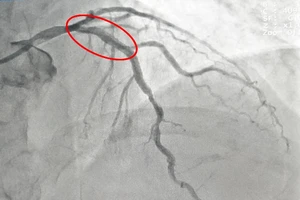

Bị nhồi máu cơ tim cấp khi đang uống bia